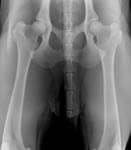

Gesundheitsstatus vom 26.11.2018 Die Röntgenbilder zeigen keinen Hinweis auf HD oder ED bei Lena vom Gehrensee. Die veterinärmedizinischen Untersuchungen von Jana auf HD, ED u. DCM und die Zuchtzulassungsprüfung wurden erfolgreich bestanden.

Die Gelenke sind HD und ED - frei, das Herz ohne Befund. Vor dem Hintergrund, dass seit 5 Generationen alle Zuchthündinnen bis ins hohe